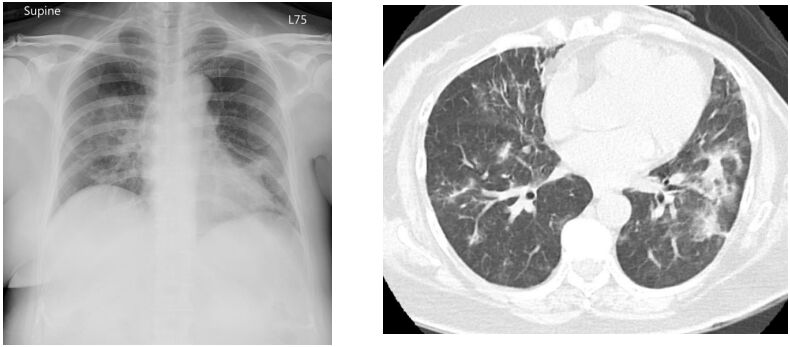

62. 一位 70 歲乳癌患者,接受 Trastuzumab-Deruxtecan 一段時間後,產生呼吸喘的狀況, 其 CXR 和 CT scan 如圖,關於其肺功能變化,下列何者錯誤?(A) FEV1/FVC 正常。 (B) FVC 下降。 (C) FEV1 下降。 (D) DLCO 上升。